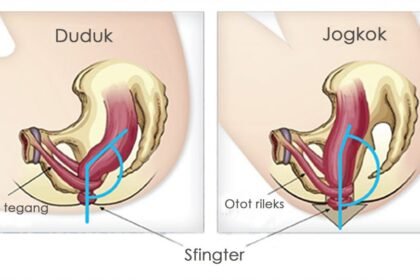

Perbandingan Kesehatan: BAB Jongkok vs Duduk

Aktivitas buang air besar (BAB) sering kali dianggap remeh, padahal memiliki dampak signifikan terhadap kesehatan…